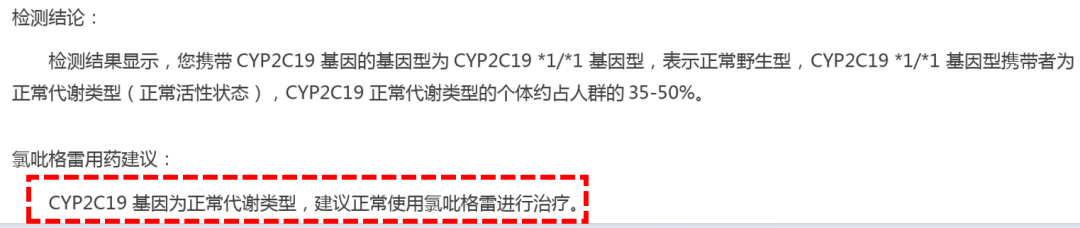

术前准备

药物准备:1、阿司匹林肠溶片100mg qd*5天,2、氯吡格雷片75mg qd*5天

抗血小板药物治疗

术后:阿司匹林肠溶片100mg qd*长期+氯吡格雷片75mg qd*3月